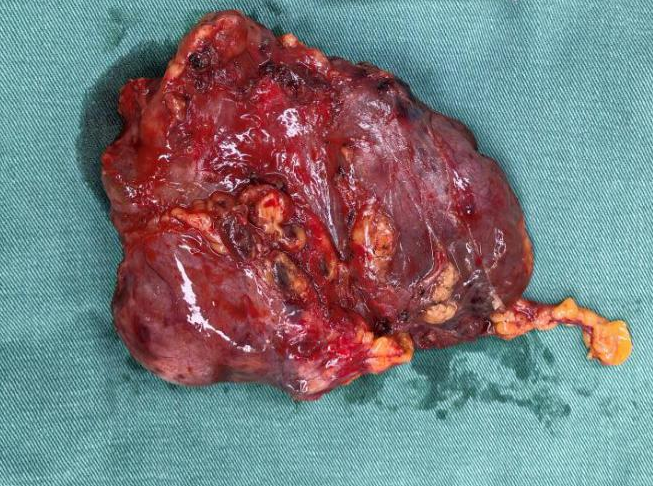

被切除的腫瘤

術前胸心血管外科團隊聯(lián)合多學科評估風險,確定手術方式、風險防范與圍手術期應急方案。術中,胸心血管外科副主任呂忠柱主任醫(yī)師主刀,通過正中胸骨切開手術,憑借精準操作避開致命陷阱,成功拆除前縱隔巨大腫瘤、完成胸腺擴大切除,同時清掃了周圍淋巴結,在保證安全的前提下達到了R0切除。手術過程順利,術后患者順利脫機拔管,已順利康復出院。